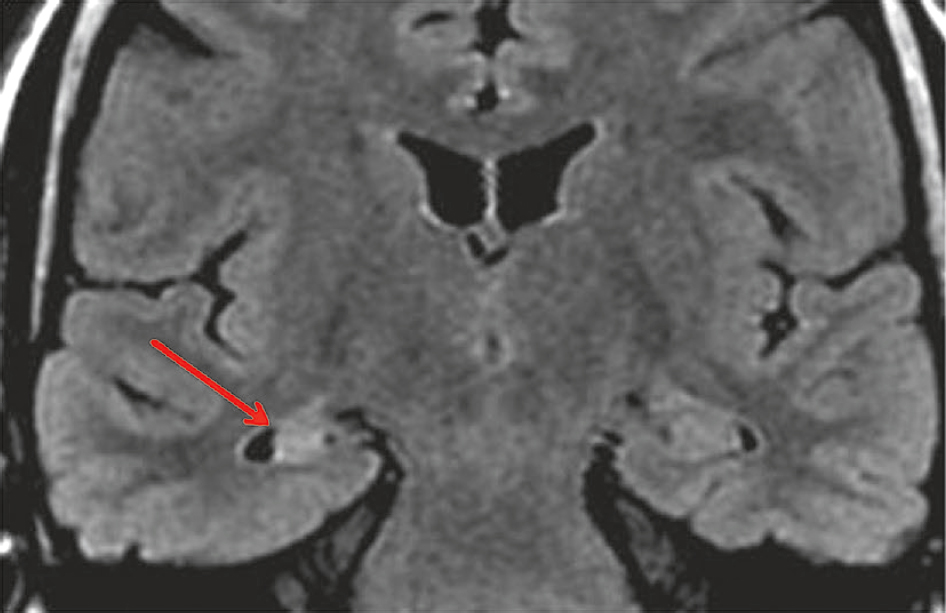

• IRM : aspect de sclérose hippocampique unilatérale (fig. 16.4).

Fig. 16.4

IRM cérébrale en coupe coronale et séquence FLAIR montrant une atrophie associée à une sclérose (hypersignal) de l’hippocampe droit (flèche rouge).L'image montre une IRM cérébrale en coupe coronale utilisant la séquence FLAIR, qui permet de détecter des anomalies cérébrales en supprimant le signal du liquide céphalorachidien. Sur cette image, on observe une atrophie associée à une sclérose (hypersignal) de l'hippocampe droit, indiquée par une flèche rouge. L'hippocampe est une structure cérébrale cruciale pour la mémoire et l'orientation spatiale. L'atrophie signifie une réduction du volume de l'hippocampe, tandis que la sclérose désigne une zone de tissu durci ou cicatriciel, visible comme un hypersignal sur les séquences FLAIR. Cette combinaison d'atrophie et de sclérose est souvent associée à des conditions neurologiques comme l'épilepsie temporale médiale, où l'hippocampe est fréquemment affecté. La détection de ces anomalies par l'IRM est essentielle pour diagnostiquer et comprendre les troubles neurologiques, en visualisant précisément les altérations structurelles du cerveau. En résumé, l'IRM révèle une atrophie et une sclérose de l'hippocampe droit, fournissant des informations importantes pour l'évaluation des conditions neurologiques.